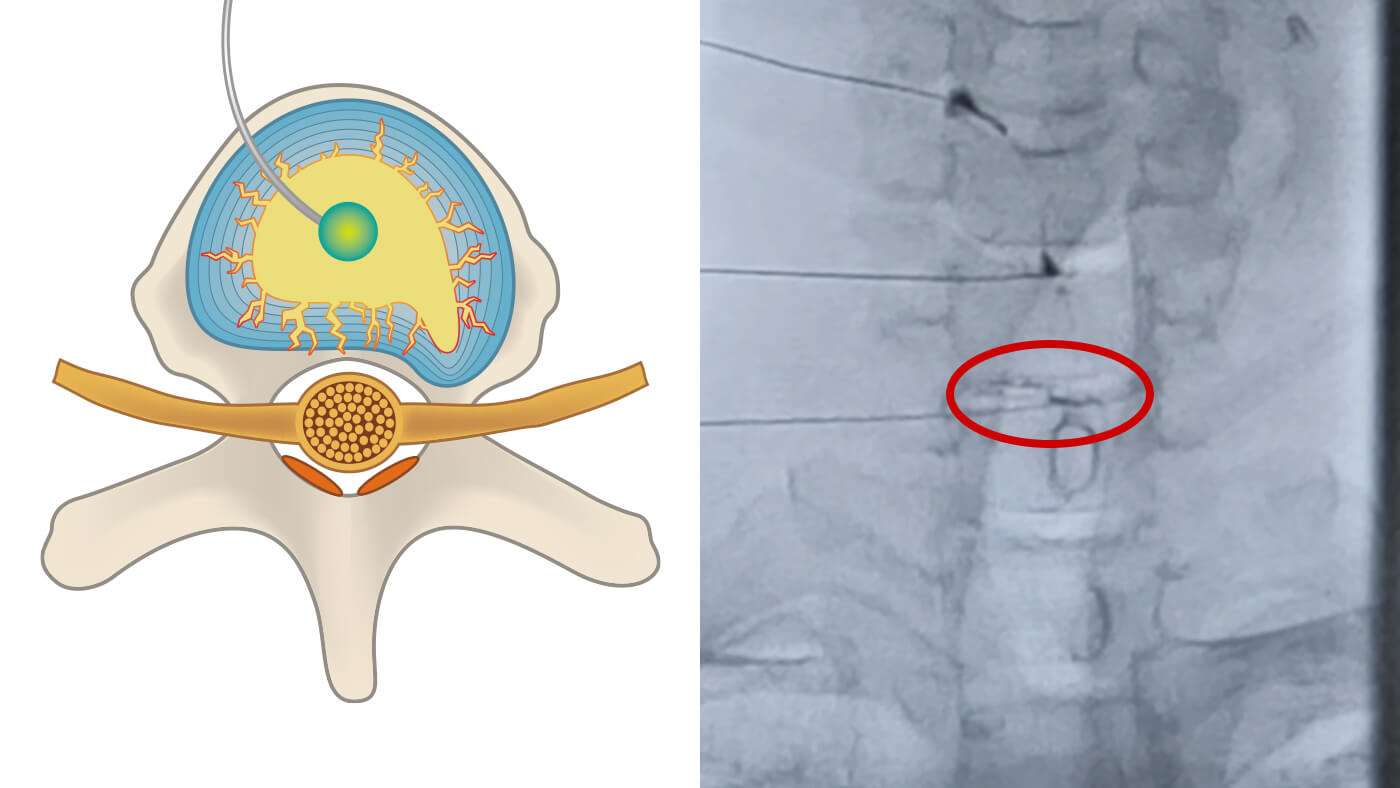

2. 治療薬の注入の図解

治療薬の注入

特定された損傷部位に穿刺針(せんししん)を用いて、治療薬を微細な精度で直接注入します。

3. 亀裂の密封と修復の図解

亀裂の密封と修復

注入された薬剤が椎間板の亀裂を徐々に塞ぎ、組織の自然な修復を促します。